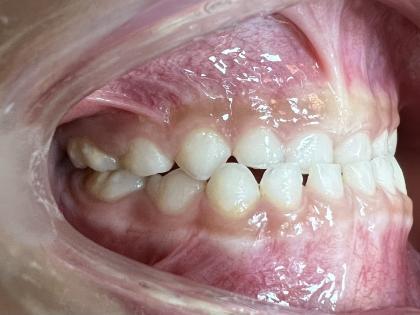

案例二:

治疗前

治疗后